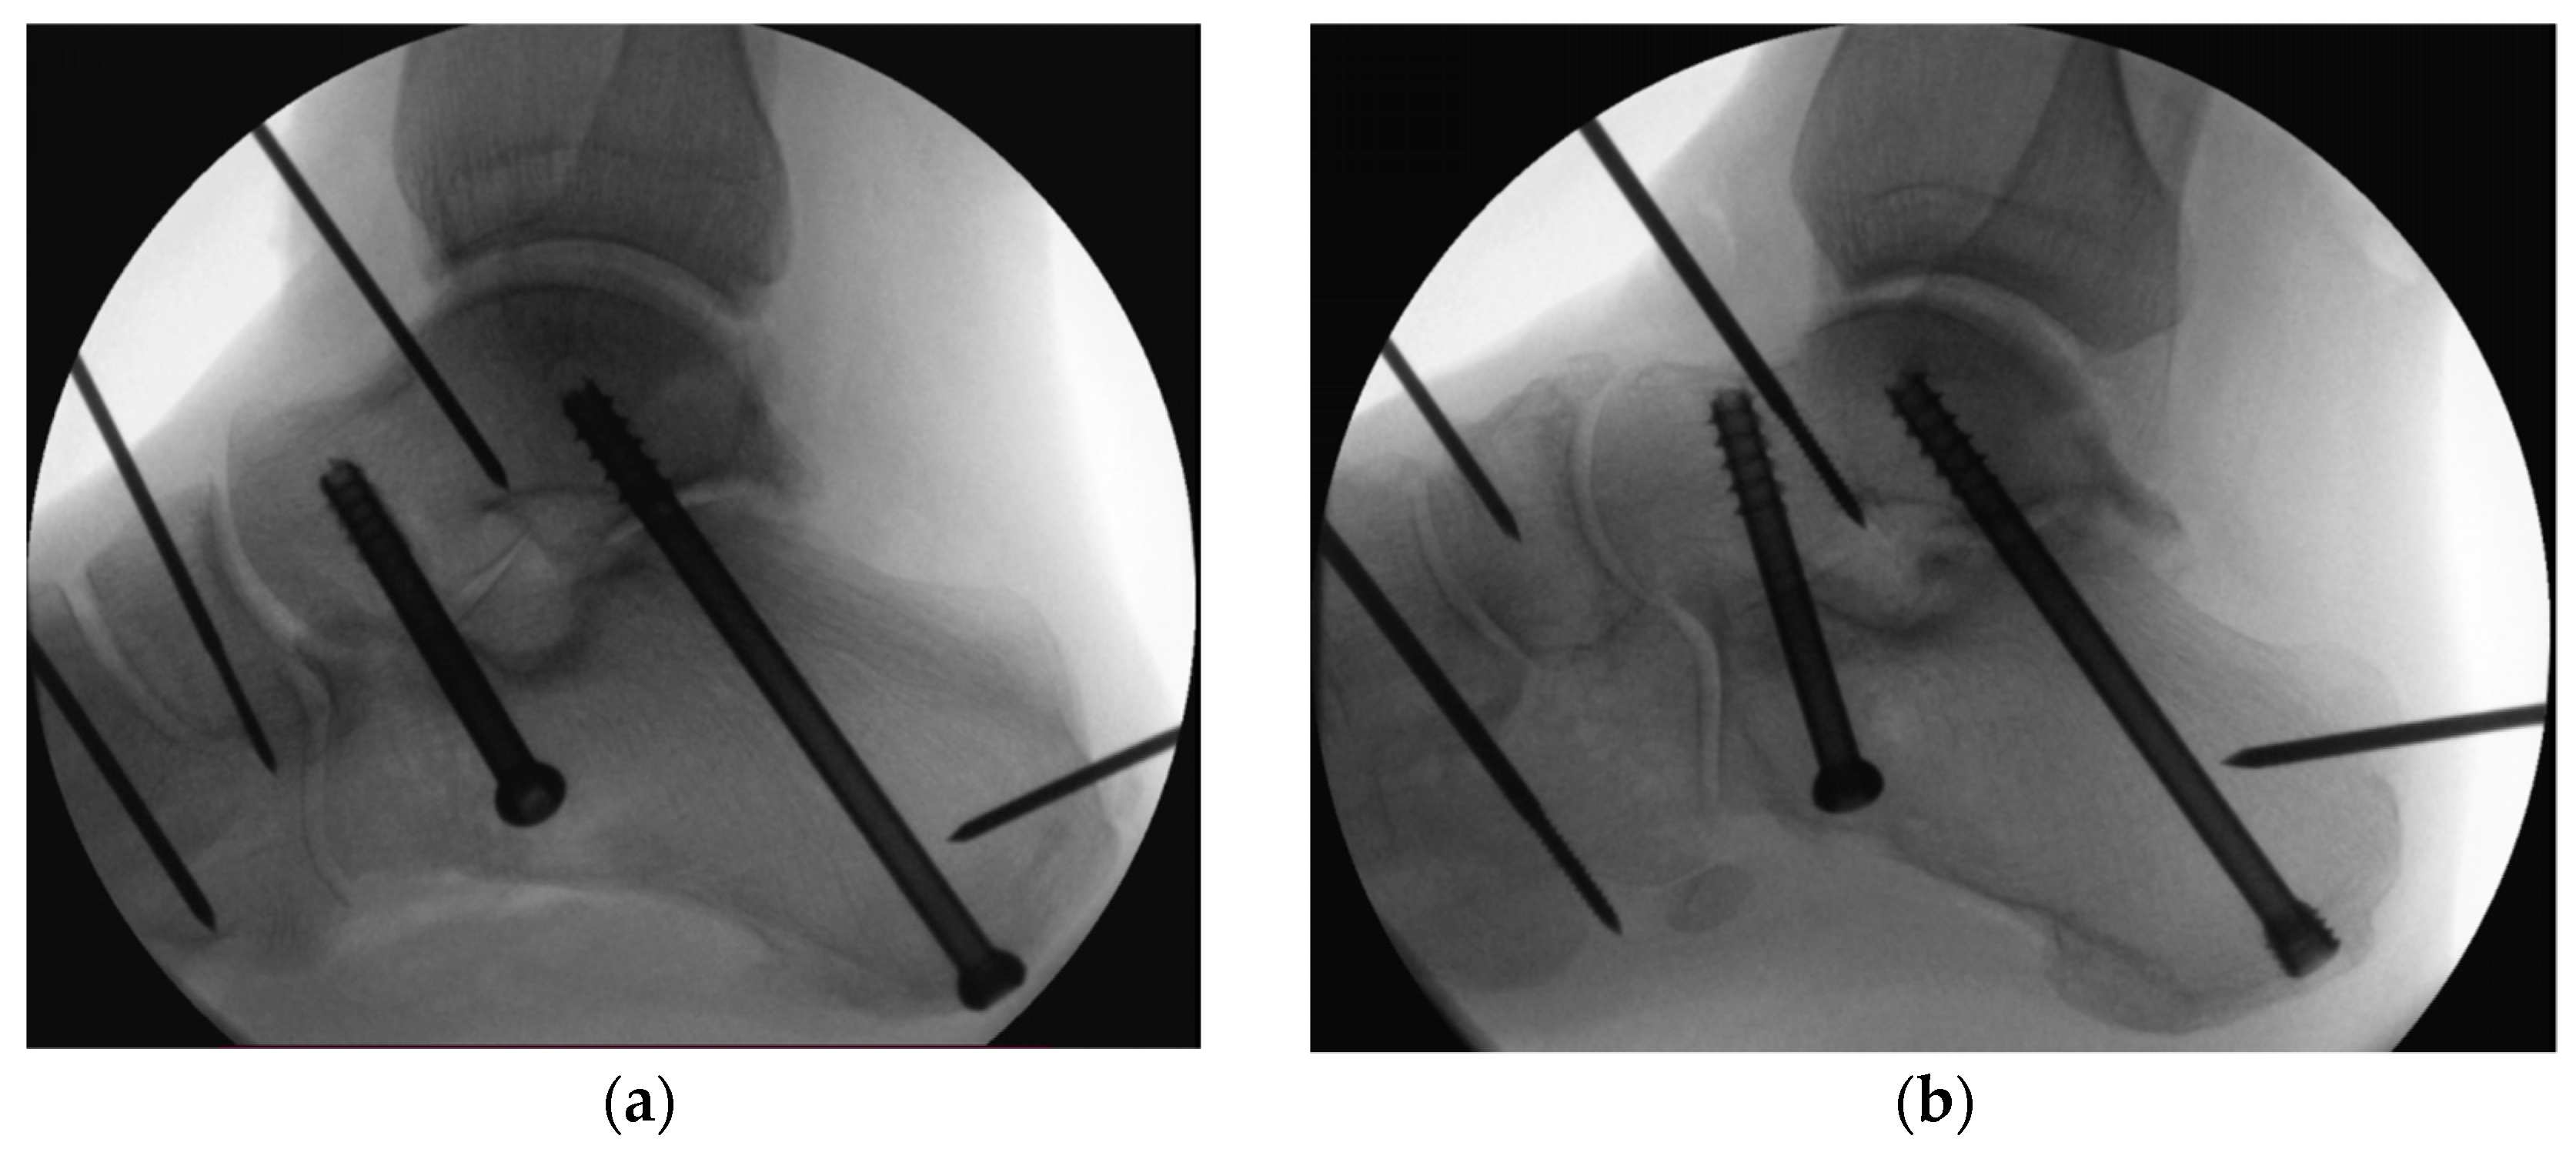

2. Materials and Methods

2.1. Specimens and Preparation

2.2. Biomechanical Testing